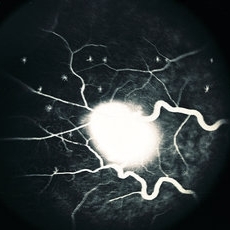

Retinal Capillary Hemangioblastoma

Fluorescein angiogram of a retinal capillary hemangioblastoma associated with Von Hippel-Lindau Disease. No history. Dilated, tortuous afferent and efferent vessels are shown. Fluorescein leakage is beginning in the rather early frame.

Condition/keywords: retinal capillary hemangioblastoma